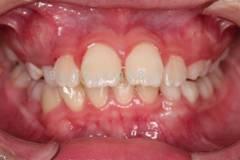

下面這個(gè)小患者就存在需早期矯正的問題。通過早期矯正,在不長(zhǎng)的時(shí)間內(nèi)就達(dá)到極為明顯的療效。她的情況如果等到牙齒替換完畢后再解決,矯治的難度則會(huì)非常大。

早期矯正中